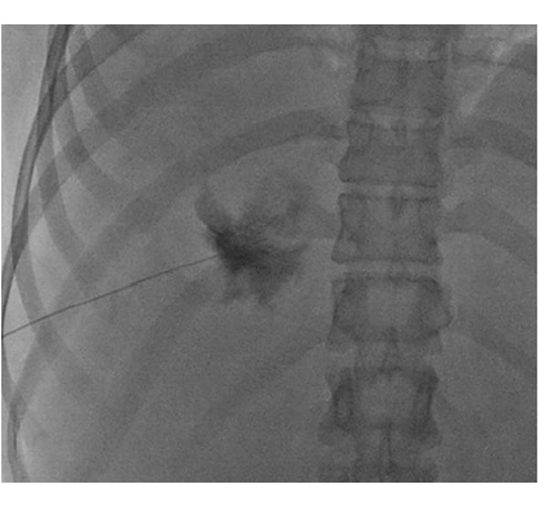

This single-institute prospective study was conducted between September 2018 and July 2020. Percutaneous sclerotherapy was performed using a mixture of bleomycin and ethiodized oil under guidance of US and fluoroscopy in participants with GLH who were experiencing related abdominal pain or fullness. Technical success was recorded. Change in symptom severity, according to visual analog scale (VAS), was considered the primary outcome of the study. Volume change, based on the lesion volume at CT, and complications, based on the classification of the Society of Interventional Radiology, were regarded as secondary outcomes. The primary and secondary outcomes were recorded 6 and 12 months after the procedure. Comparison was performed by using the Wilcoxon signed-rank test or paired t test.

Twenty-eight participants (mean age, 45 years ± 9; 25 women) were evaluated. Technical success was 100%. The mean VAS score was 8.3 before the procedure, which decreased to 1.4 (84.7% reduction) and 1.5 (83.5% reduction) at 6- and 12-month follow-ups, respectively (P < .001 for both). All participants reported relief of symptoms (17 of 28 participants [61%] with complete relief; 11 [39%] with partial relief) at 12-month follow-up. Mean GLH volumes dropped from 856.3 cm3 to 309.8 cm3 (65.7% reduction) and 206.0 cm3 (76% reduction) at 6- and 12-month follow-ups, respectively (P < .001 for both). No major complications were detected.

Percutaneous sclerotherapy is a safe and feasible method with promising results in the treatment of patients with symptomatic giant liver hemangioma.